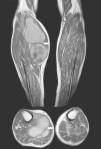

We present the case of an 83-year-old male patient with osteoarthritis, who came to the emergency room due to acute inflammation of the leg simulating DVT. On physical examination, there was a mass of elastic consistency, non-pulsatile, painful, in the popliteal fossa, extending to the leg (Fig. 1). The differential diagnosis was made with Baker cyst. The patient underwent, as a technique of choice, an ultrasound. The color Doppler mode showed patency of the deep venous system. Musculoskeletal ultrasound evidenced a well-defined collection, adjacent to the medial gastrocnemius muscle belly, full of vague echoes predominantly of low amplitude (Fig. 2) Despite being frequent, the size of the tumor made ultrasound insufficient and we decided to perform specific knee MRI with T1 potentiated sequences, T2* sequences (Figs. 3–5) and, after administration of intravenous contrast, we confirmed the existence of giant popliteal cyst of 17cm×9cm. The patient was treated conservatively, using, in the first place, nonsteroidal anti-inflammatory drugs, with clinical improvement and asymptomatic after the first 6 months. For this reason, along with the age of the patient and in spite of the cyst barely changing its size, surgical treatment has so far been dismissed.

Fig. 5.

MR. Sagittal T1-weighted image with fat saturation. Peripheral potentiation is observed compared to the precontrast image but no significant image central enhancement, indicating its cystic nature.